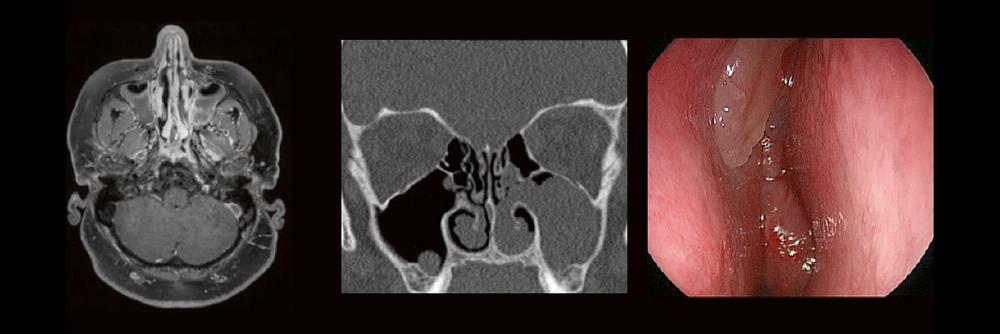

Dr. med. André ReisbergDr. med Sebastian Plößl Die bildgebende HNO-Diagnostik macht es Anfängern nicht leicht. Die Anatomie ist komplex und weniger intuitiv als in anderen Körperregionen. Normvarianten erschweren insbesondere in den Nasennebenhöhlen den Lernprozess. Sobald pathophysiologische Zusammenhänge verstanden und wichtige klinische Aspekte verinnerlicht wurden, gelingt es einen praxistauglichen, belastbaren Befund zu erstellen. Wo muss ich